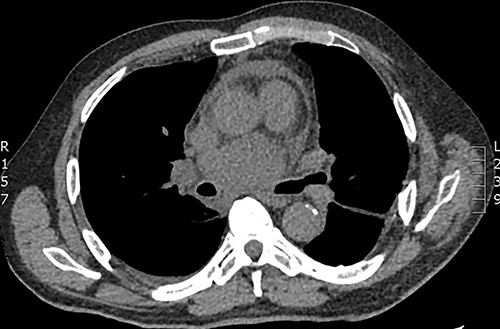

The second case was a 31-year-old gentleman otherwise fit and well was admitted to hospital with community acquired pneumonia and underwent intravenous antibiotic therapy. CT imaging demonstrated mediastinal lymphadenopathy and an incidental large subcarinal mass. The patient underwent EBUS biopsy of the subcarinal mass, which did not retrieve any tissue. Following discharge from hospital the patient represented 5 days later with pyrexia and chest pain. Repeat CT imaging demonstrated a rim enhancing lesion with cystic features and indenting the right pulmonary artery (Fig. 2). The patient was commenced on broad spectrum antibiotic therapy however remained pyrexial with rising inflammatory markers and was transferred to our institution for urgent surgery. The patient underwent urgent right posterolateral thoracotomy and deroofing of mediastinal cyst. Operative findings were that of an infected subcarinal cyst with pus within the cyst and dense adhesions to the surrounding structures. The cyst was excised from the surrounding structures and de-roofed. The patient returned to the high dependency unit in a stable condition and progressed satisfactorily eventually discharged from hospital 7 days following admission. Post-operative histology was consistent with an infected bronchogenic cyst and pus cells with no growth on culture.